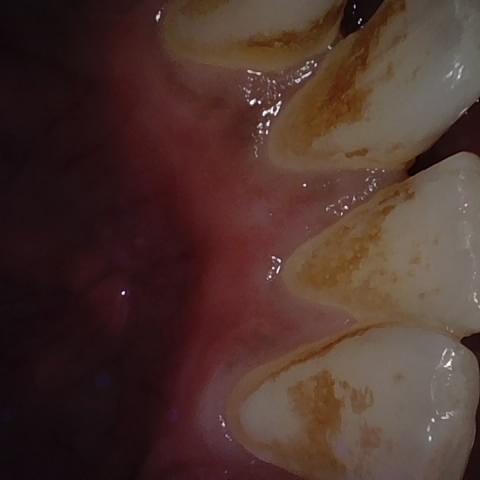

NHD38254

Annotated as "Good"